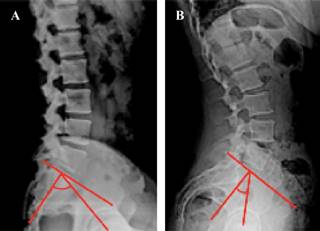

El ángulo de pendiente sacra permite determinar la magnitud de la lordosis lumbar ya que éste determina la magnitud de su curvatura; es decir, a menor pendiente, menor lordosis y a mayor pendiente mayor lordosis. Observe en la Figura 13 los efectos de la pendiente sacra en la magnitud de la lordosis lumbar.

Figura 13: A) Sacro con menor pendiente = menor lordosis y mayor incidencia pélvica. B) Sacro con mayor pendiente = mayor lordosis y menor incidencia pélvica.